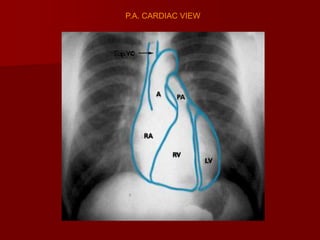

P.A. CARDIAC VIEW

Superior Vena Cava

Aortic Arch

Ascending Aorta

Pulmonary Artery

Left Atrium

Right Atrium

Left Ventricle

INFERIOR VENA CAVA